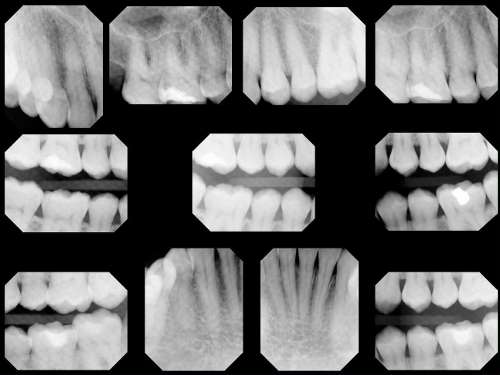

Digital X-Rays

Modern digital dental x-rays benefit patients in a number of ways:

• Digital x-rays expose patients to considerably less radiation than conventional film x-rays.

• Digital x-rays require almost no time for development, reducing time spent waiting in the dental chair.

• Digital x-rays allow for incredibly precise and accurate images for timely diagnoses.

• Digital x-rays are securely stored in your digital file and can be securely sent to your insurance company or specialists, when necessary.

Because no chemicals are needed for developing and no space is needed for film storage, digital x-rays are better for the environment.